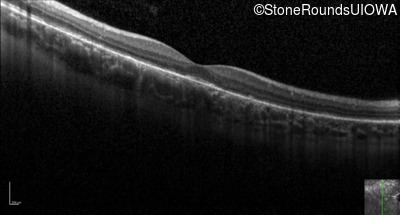

Optical Coherence Tomography - Right - 20/20 -2 sc

Exemplar / OCT Stack